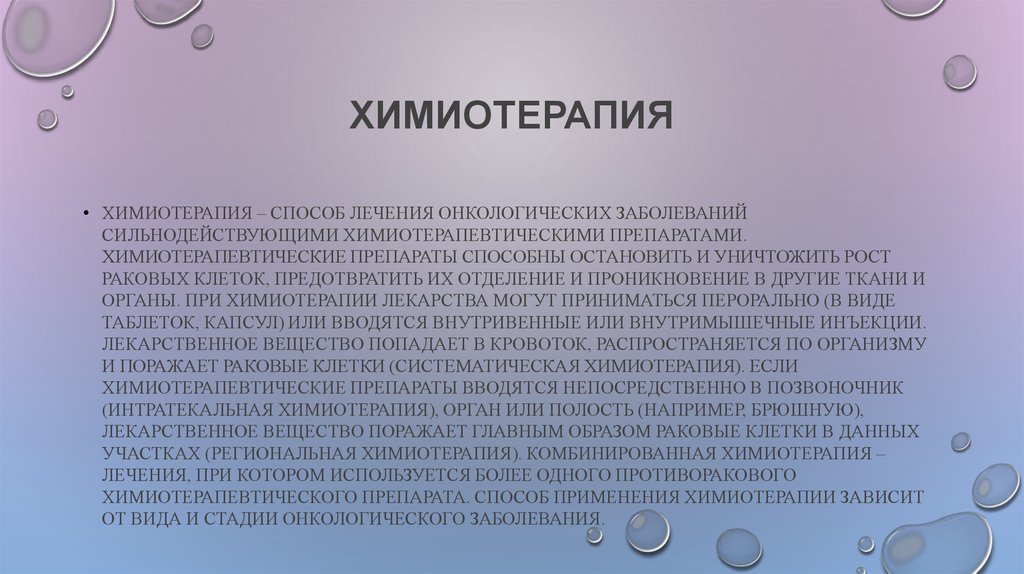

Лечение туберкулеза: Методики химиотерапии

Раздел: Визуальный дайджест